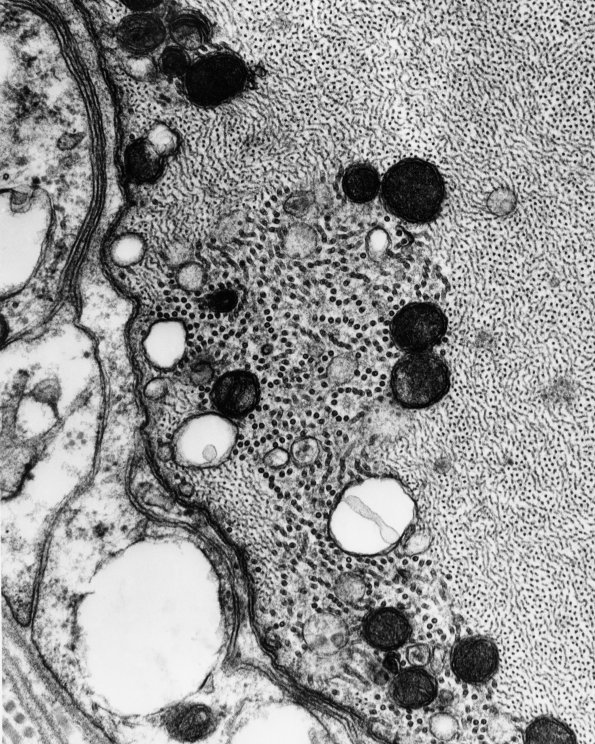

Washington University Experience | PERIPHERAL NEUROPATHY | 18 HEREDITARY DISORDERS | Giant Axonal Neuropathy (GAN) | 2B5 (Case 2) - CopyB

In this case cytoskeletal microtubules are marginated to the subaxolemma by aggregated neurofilaments. (electron micrographs)